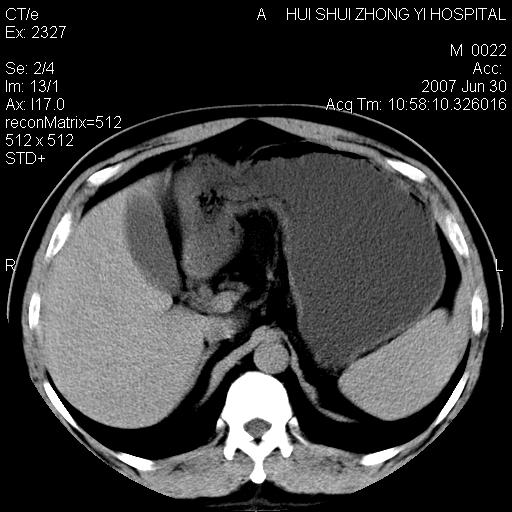

男,44岁,体检。

肝右叶密度减低区?

支持双肾结石,肝右叶低密度影为胆囊部分容积效应。

肝右叶低密度影为胆囊部分容积效应?为什么s43.0层面下来不见胆囊影,而是相隔了一层才见胆囊影。这是按我们扫描的顺序发的,但是是追加扫描的。

肝右叶低密度灶,增强!

病人呼吸动了,第四层应该在第五\\六层之间。肝右叶低密度影为胆囊部分容积效应。双肾结石。